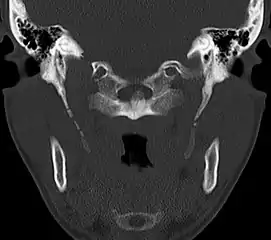

Anteroposterior and lateral radiographs of cervical spine showing ossification of the stylohyoid ligament on both sides

Imaging is important and is diagnostic. Visualizing the styloid process on a CT scan with 3D reconstruction is the suggested imaging technique.[12] The enlarged styloid may be visible on an orthopantogram or a lateral soft tissue X ray of the neck.